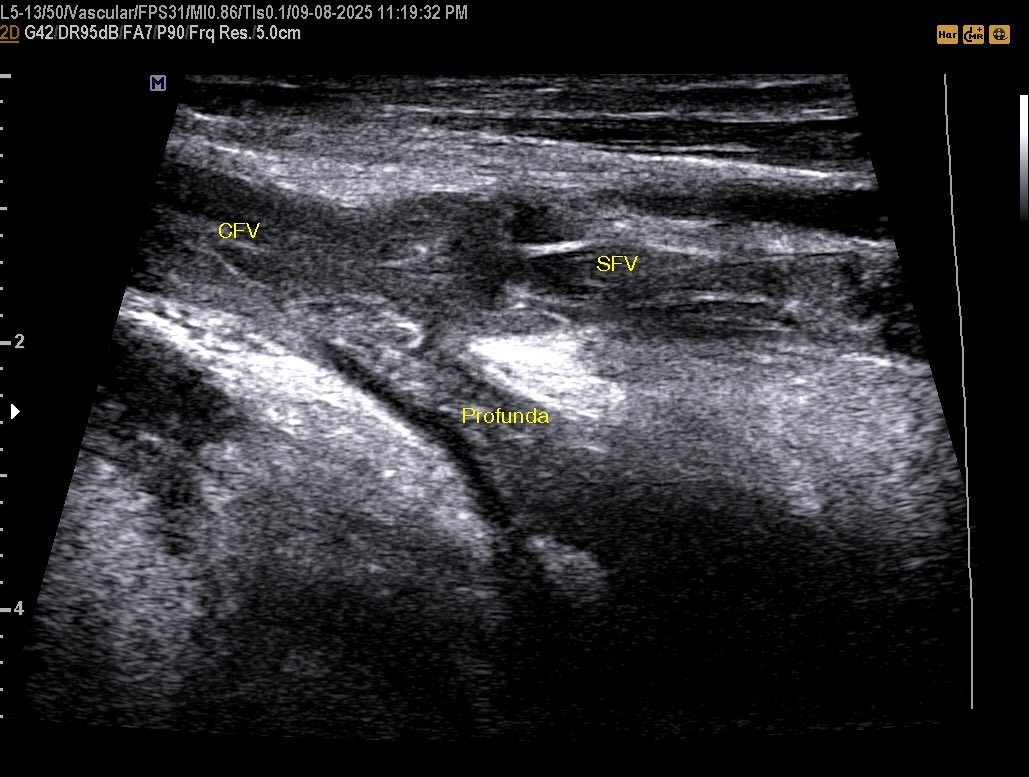

a 58 years male came with a diabetic foot And diffuse foot swelling Duplex U/S requested and done Your opinion? #EchoTech

Extensive DVT and SVT in 43 years female with a history of Ovarian cancer underwent neo adjuvant chemotherapy. In such cases the operator must assess the arterial system to exclude the possibility of Phlegmasia cerulea dolens. #EchoTech

a 58 years male came with a diabetic foot And diffuse foot swelling Duplex U/S requested and done Your opinion? #EchoTech

a 58 years male came with a diabetic foot And diffuse foot swelling Duplex U/S requested and done Your opinion? #EchoTech

a 58 years male came with a diabetic foot And diffuse foot swelling Duplex U/S requested and done Your opinion? #EchoTech

Extensive DVT and SVT in 43 years female with a history of Ovarian cancer underwent neo adjuvant chemotherapy. In such cases the operator must assess the arterial system to exclude the possibility of Phlegmasia cerulea dolens. #EchoTech